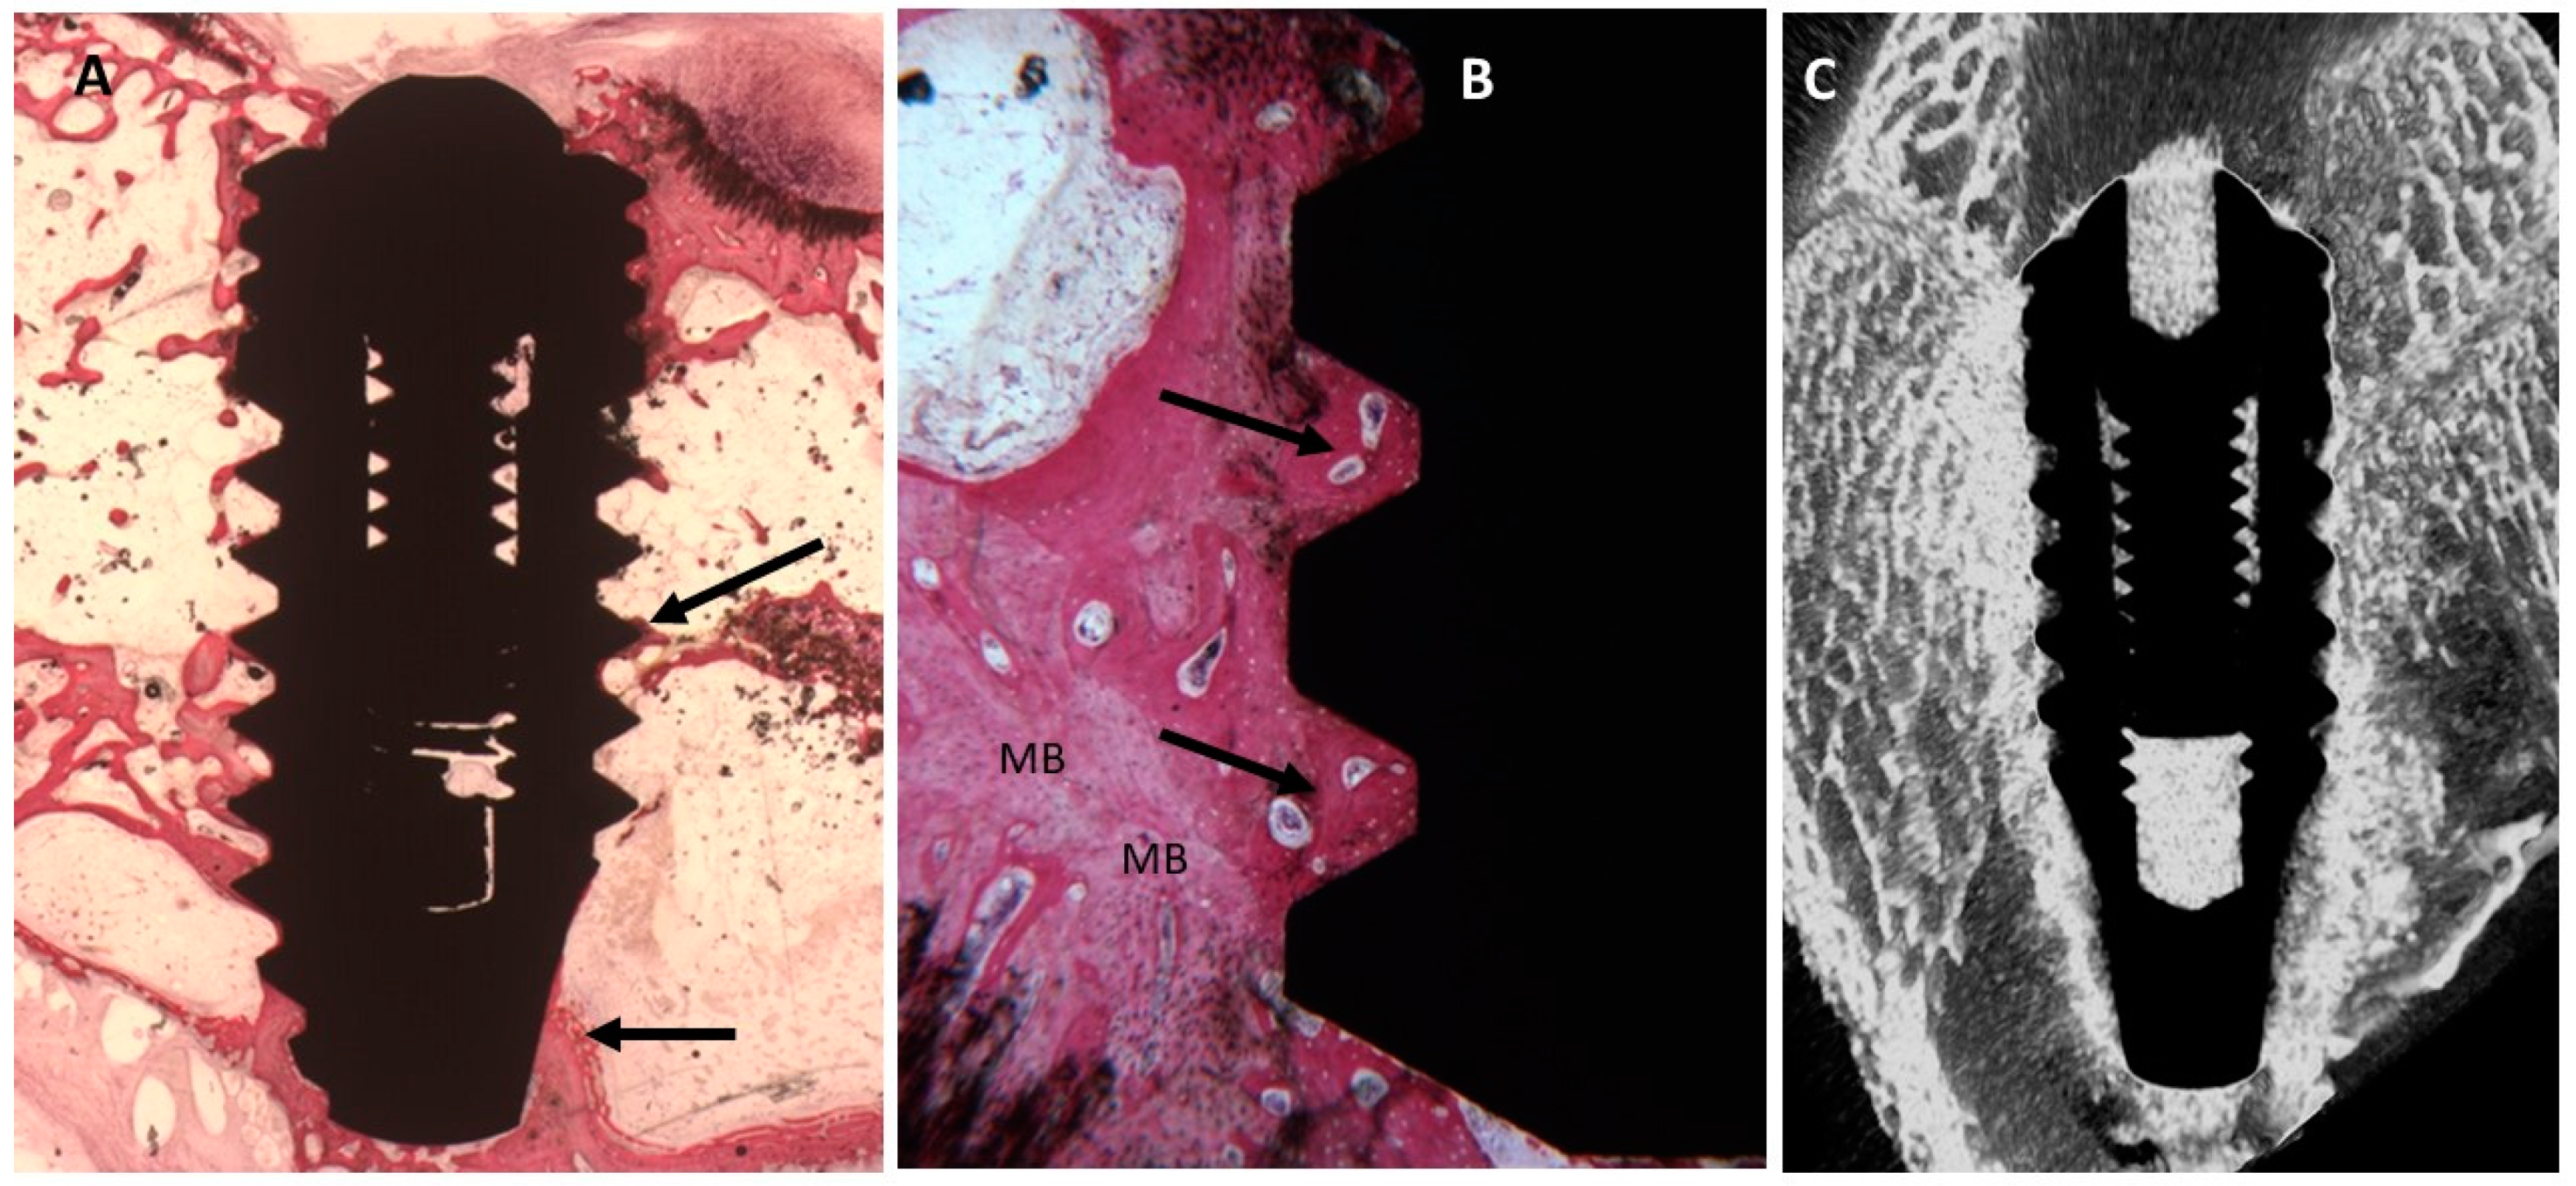

2.3. Micro-CT Evaluation

2.4. Histological Evaluation